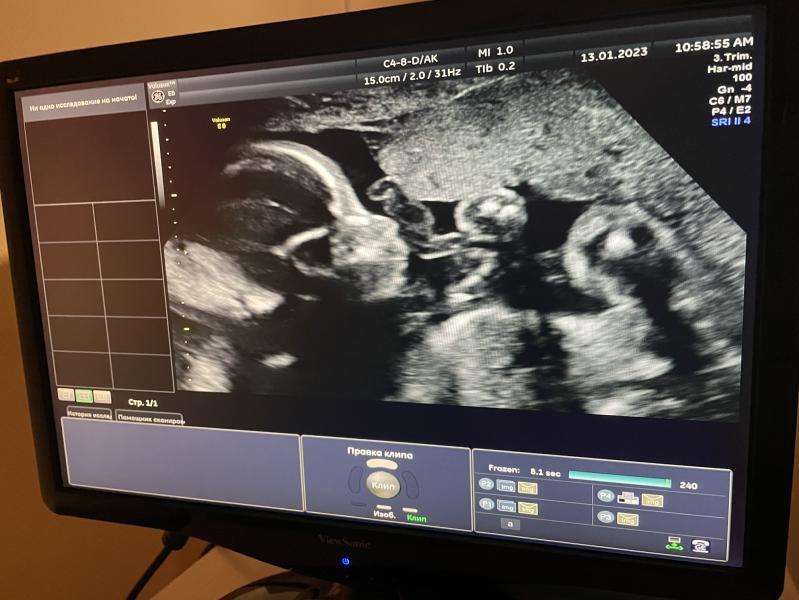

Наша принцесса 🙃🌺

Ходила сегодня на Доплер, все артерии в норме🙈 Я так боялась что будут проблемы…